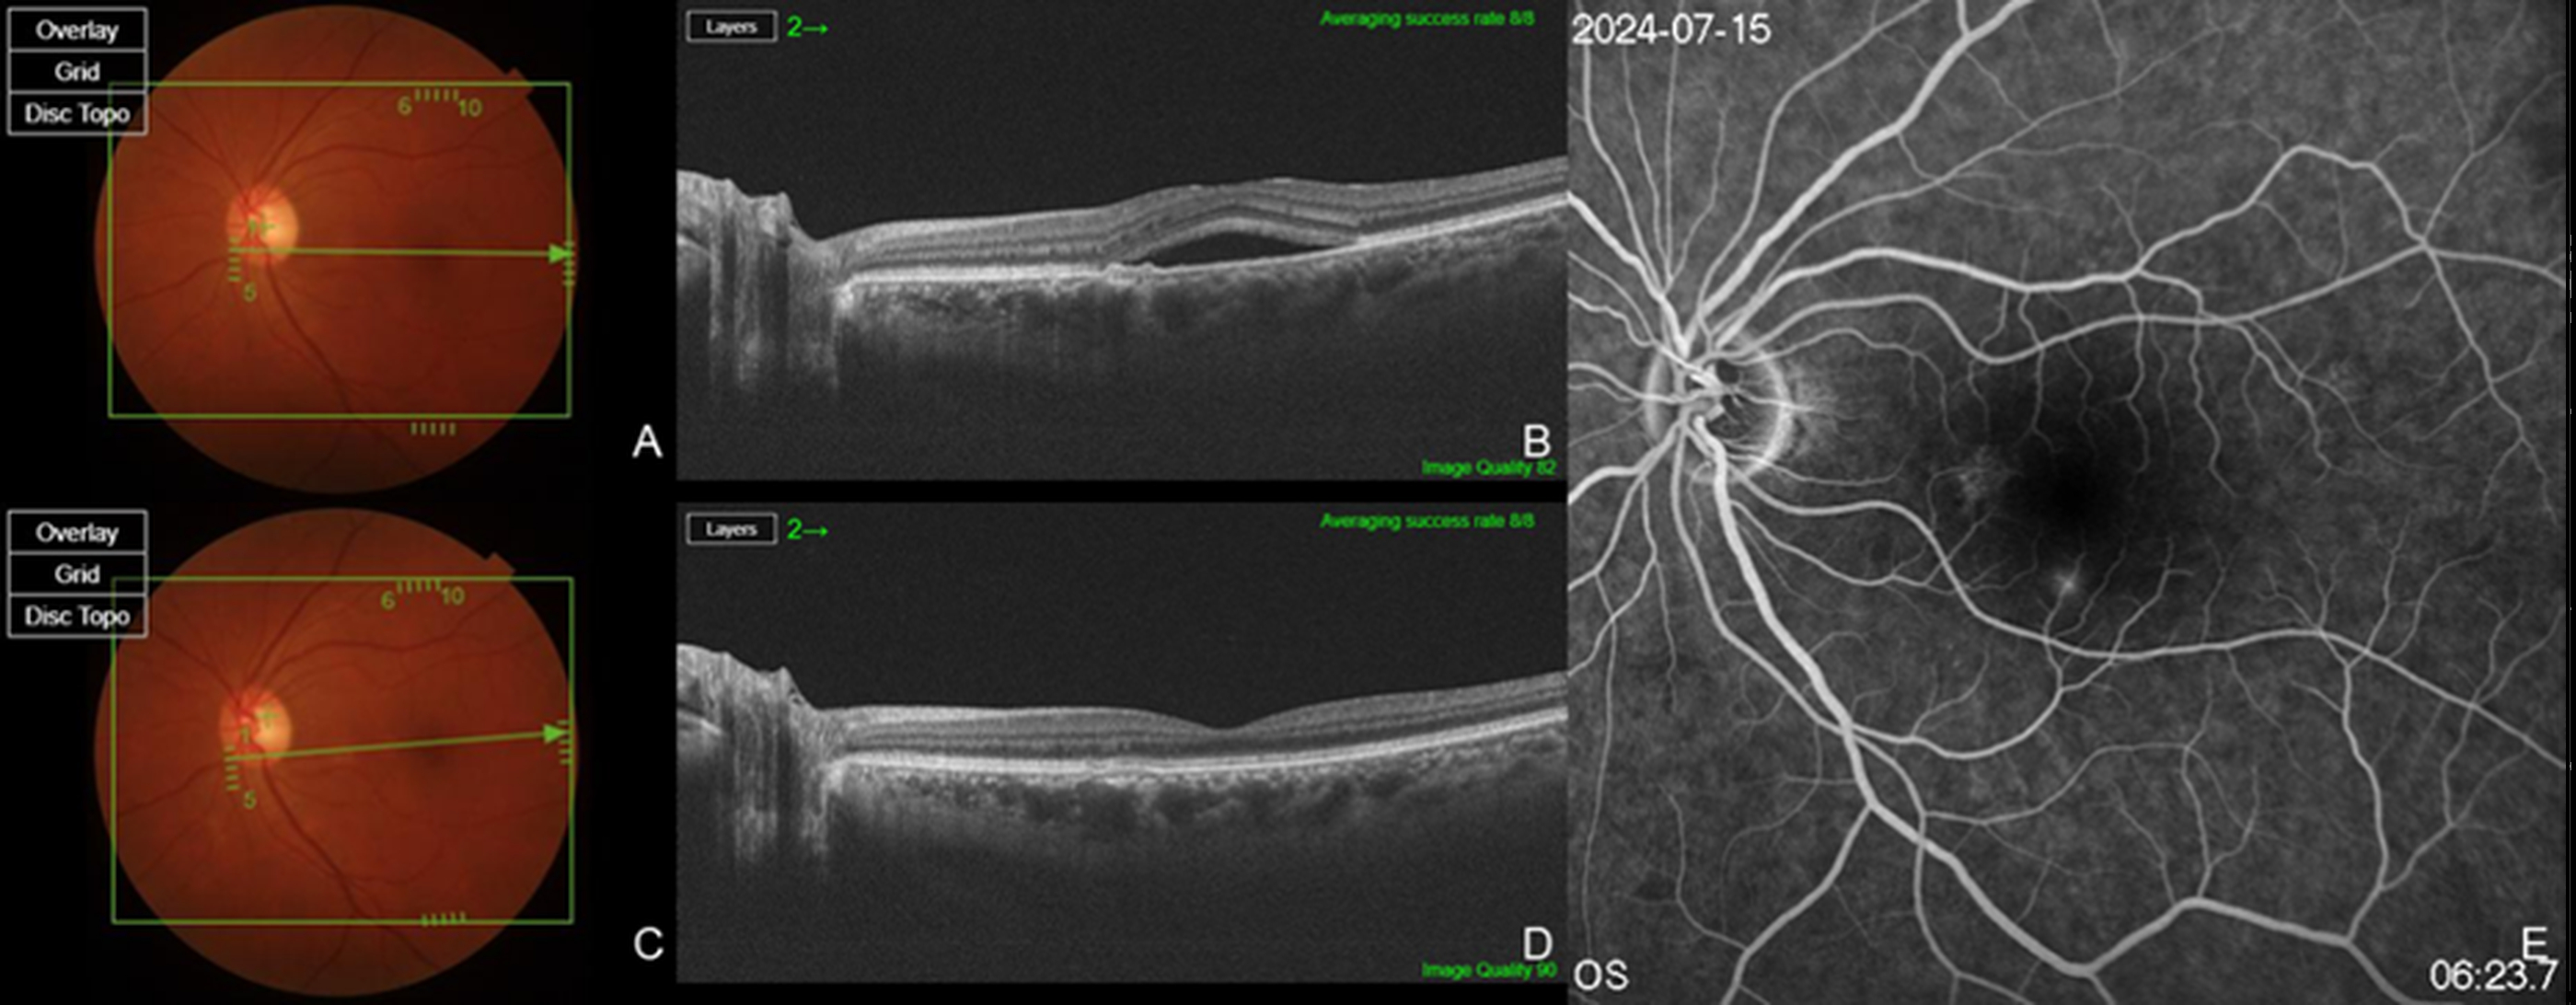

Figure 1. Multimodal retinal imaging in a treatment-naïve patient with chronic central serous chorioretinopathy (cCSC). Baseline fundus photography (A) and swept source (SS)-optical coherence tomography (OCT) (B) show mild pigment epithelial detachment (PED) and subretinal fluid (SRF) at the macula. At one month after intravitreal injection of brolucizumab, fundus photography (C) and SS-OCT (D) demonstrate complete resolution of SRF and significant reduction in PED height. Fluorescein angiography (E) reveals minimal leakage without evidence of pachychoroid neovasculopathy (PNV) or polypoidal lesions, supporting the diagnosis of uncomplicated cCSC. Subfoveal choroidal thickness (SCT) decreased from 401 μm at baseline (B) to 208 μm (D) after injection.

Figure 2. Therapeutic response after switching to brolucizumab in a previously treated patient with bevacizumab. Baseline fundus photography (A) and SS-OCT (B) demonstrate persistent SRF and PED, despite six prior intravitreal bevacizumab injections. One month after the last bevacizumab injection, SRF and PED remain unchanged, as shown by fundus photography (C) and SS-OCT (D). Following a switch to intravitreal bolucizumab, fundus photography (E) and SS-OCT (F) at one month post-injection reveal complete resolution of SRF and significant reduction in PED height, indicating superior anatomical efficacy of brolucizumab in this refractory case. While the SCT value remained nearly unchanged from a baseline of 705 μm (B) to 701 μm (D) after bevacizumab injection, it decreased to 643 μm (F) one month after brolucizumab administration.